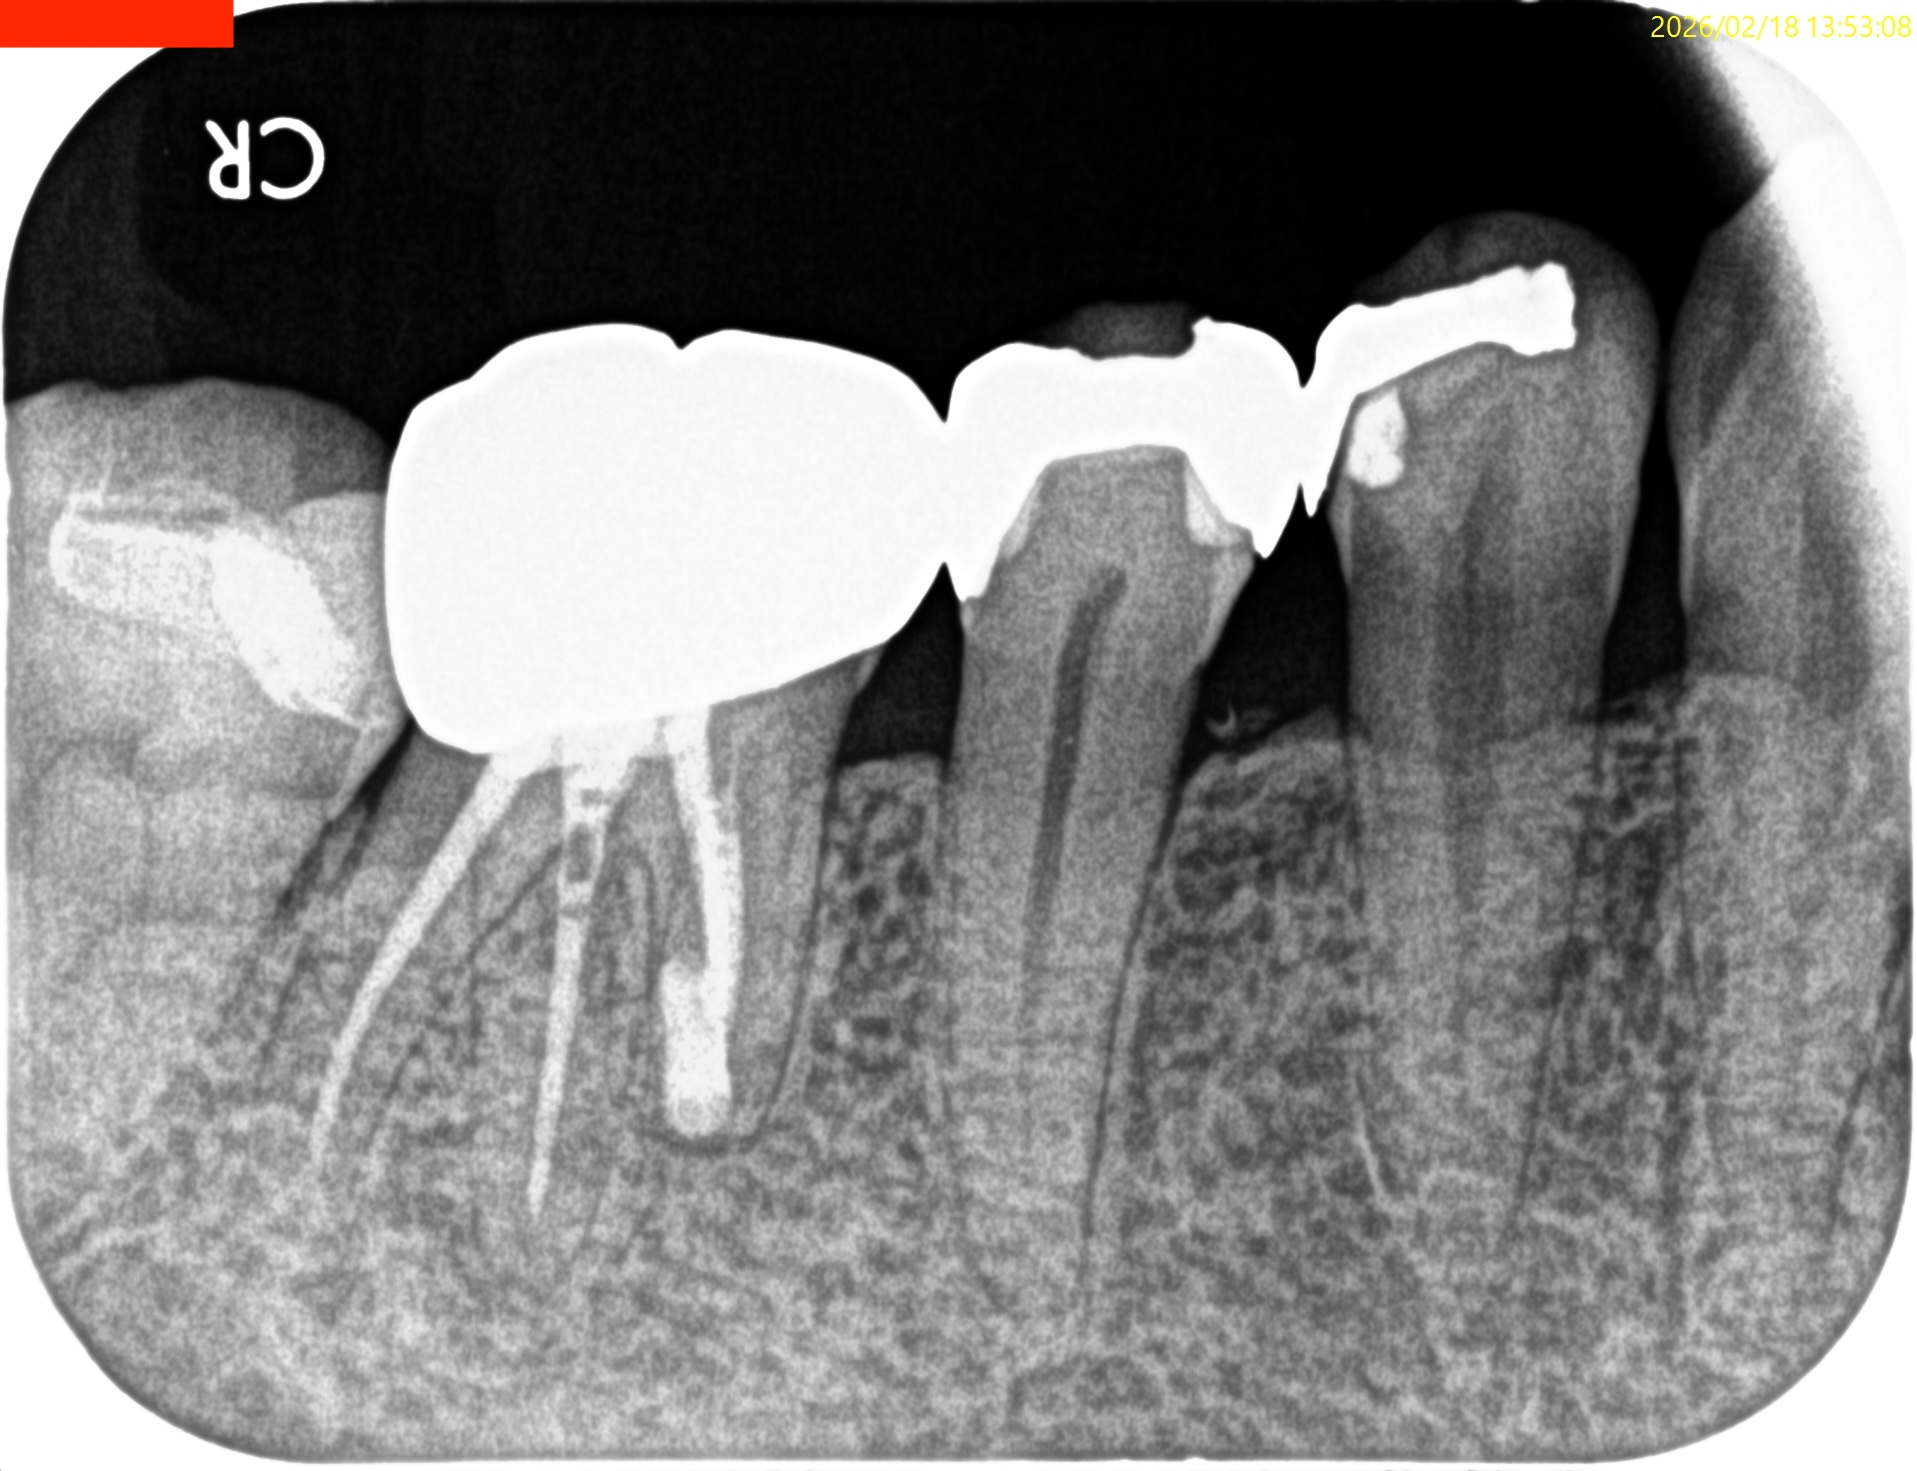

#30 M Apicoectomy 6M recall(2026.2.18)

大幅に問題が改善している。

初診時と比較した。

歯槽骨が劇的に再生している。

臨床症状もない。